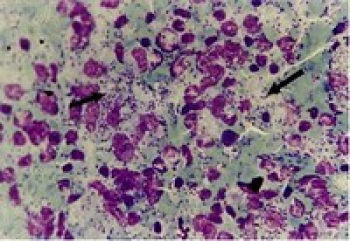

Entamoeba histolytica insanların sindirim sisteminde hastalık yapan tek amip türüdür. Bağlrsak duvarına yerleşerek yüzeysel ya da derin yaralar açar. Asalak bazen bağırsak duvarım delerek karaciğere ve bağırsak dışı başka organlara da ulaşabilir. Asalağın iki evresi vardır. Bunların biri asalağın beslenip büyüdüğü ve çoğaldığı etkinlik evresidir. Öbürü ise etkinliğe uygun olmayan koşullarda çevresinde bir kist oluşturduğu kistli evredir; asalak kistli evrede ise bir konaktan öbürüne geçer. Etkin çoğalma evresindeki (trofozo-it) asalak, dokularda ve sulu dışkıda bulunur. Kanla beslenen bu asalaktan yalnızca daha küçük olmasıyla ayırt edilebilen E. hartmanni ise bağırsakta hastalık yapmadan (saprofit olarak) yaşar. Körbağrrsak ya da çıkan kalınbağırsak duvarına yapışarak buradaki besin artıklarıyla beslenir. Bağırsak içeriğiyle birlikte kalınbağırsağın son bölümlerine sürüklendiğinde tıpkı E. histolytica gibi daha zor yaşam koşullarına dayanabilmek için kistli hale dönüşür ve bu biçimde dışkıyla atılır. Kistler dış ortamda uzun süre yaşayabilir. Ağız yoluyla başka bir organizmaya girince yeni konağm bağırsağında bir kez daha etkinlik evresine girerler. Hastalık yapıcı döngünün neden her insanda tamamlanmadığı, henüz bilinmemektedir. Ama bu döngü tamamlanınca asalak ürettiği enzimlerle bağırsak duvarını yıkıma uğratır; hatta bazı olgularda duvar engelini de aşar. Bağırsak enfeksiyonu yapan tek amip türü olan Entamoeba histolytica bağırsak duvarını delerek başta karaciğer olmak üzere öbür iç organlara da yerleşebilir. Amipler bağırsak mukozasının altında ürer ve bağırsak duvarında gömlek i düğmesini andıran yaraların (ülser) { oluşmasına yol açar. Bu yaralar küçük ama derindir. Bazı durumlarda doku j ölümü derinleşerek bağırsak duvarının 1 delinmesine, karın zan apselerine ve kanamalara yol açar. Bazı olgularda ise bu yaraların içi onarım dokusuyla (gra-nülasyon dokusu) dolarak ameborn denen tümöre benzer düğümcükler oluşturur. Bağırsak duvarındaki yaralar genellikle kapanır, arna zamanla bağırsakta kalıcı bir darlık gelişebilir. Bazı olgularda ise trofozoitler sindirim sisteminin ana toplardamarı olan kapı toplardamarı yoluyla karaciğere ulaşır. Amiplerin kalınbağırsak mukozasına yerleşmeleri çeşitli biçimlerde sonuçlanabilir.